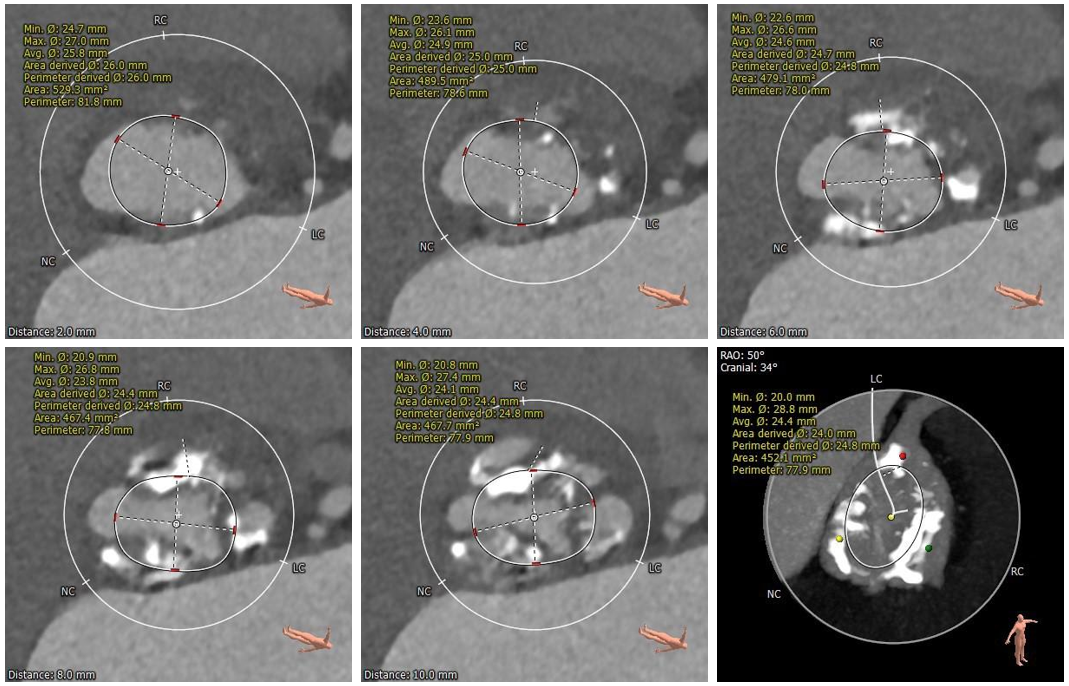

术前CT评估

•三叶式主动脉瓣,瓣环径为33.9mm,瓣环明显增大,瓣叶增厚伴重度钙化,钙化主要分布于瓣叶边缘,以右冠瓣为著;

•冠脉开口高度可,切线角度测量未见冗长瓣叶;

•瓦氏窦、窦管交界内径尚可,升主动脉扩张;

•左室腔内径明显增大,心室壁厚度尚可;

•瓣环水平夹角为62°,主动脉弓宽度、角度尚可;升主动脉轻度扭曲;

•主动脉弓、腹主动脉下段、双侧髂总动脉可见散在钙化斑块,双侧股髂动脉未见明显扭曲,股动脉穿刺处未见钙化斑块,入路血管直径尚可。

主动脉根部测量